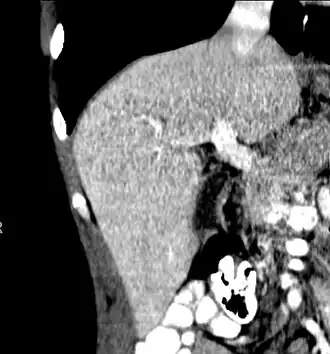

A CT scan in which the liver and portal vein are shown